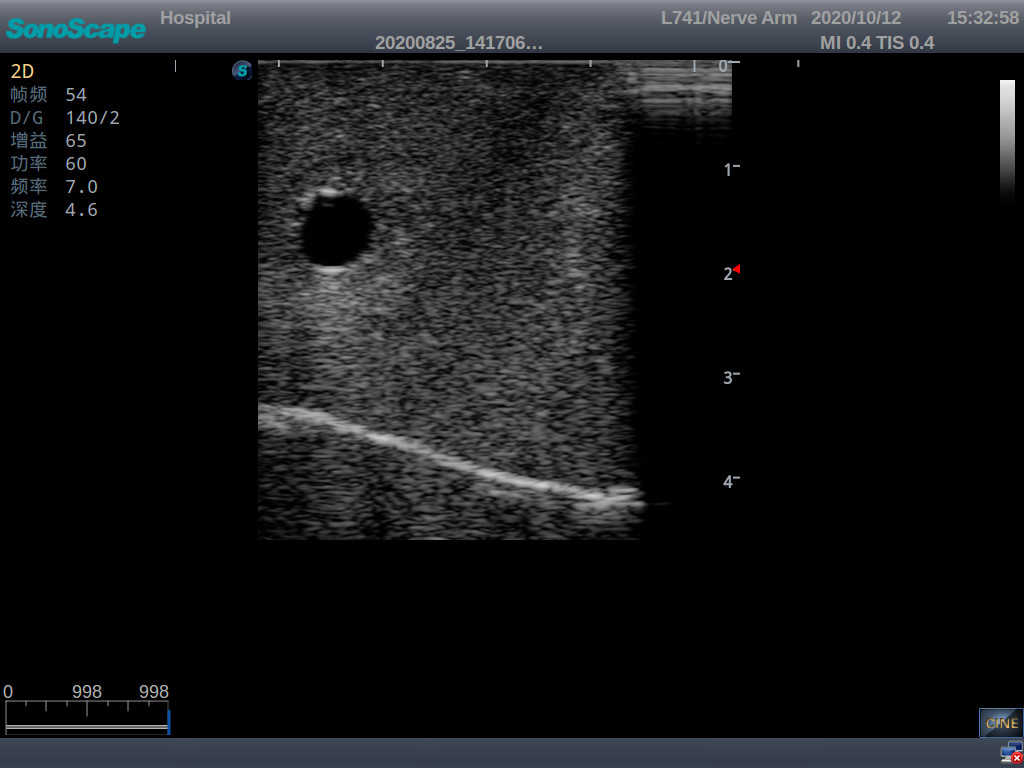

Central Venous Catheterization Ultrasound Training Model

It is a model from the earlobe plane to the umbilical plane with its head turned to one side. It's put in a standard central venipucture and catheterization position, including landmarks such as right arm, clavicle, ribs, sternocleidomastoid muscle, sternoclavicular joint, etc. It can be used for ultrasound-guided subclavian vein and internal jugular vein puncture and catheterization. The model's arm can be used for ultrasound-guided PICC catheter placement.

2)  The puncture module supports using a clinical real ultrasound machine to observe clear images such as right internal jugular vein, right common carotid artery, superior vena cava, right brachiocephalic vein, right brachiocephalic trunk, right subclavian vein, right subclavian artery, etc.

3)  The puncture pad at the arm is made of high-molecular ultrasound material, close to real skin. It can support the use of real ultrasound machines, and the images of tissue structures (skin, subcutaneous tissue, blood vessels) under ultrasound are clear and real

5)  The guide wire’s march can be observed under the guidance of ultrasound, and also whether the catheter is placed correctly can be detected